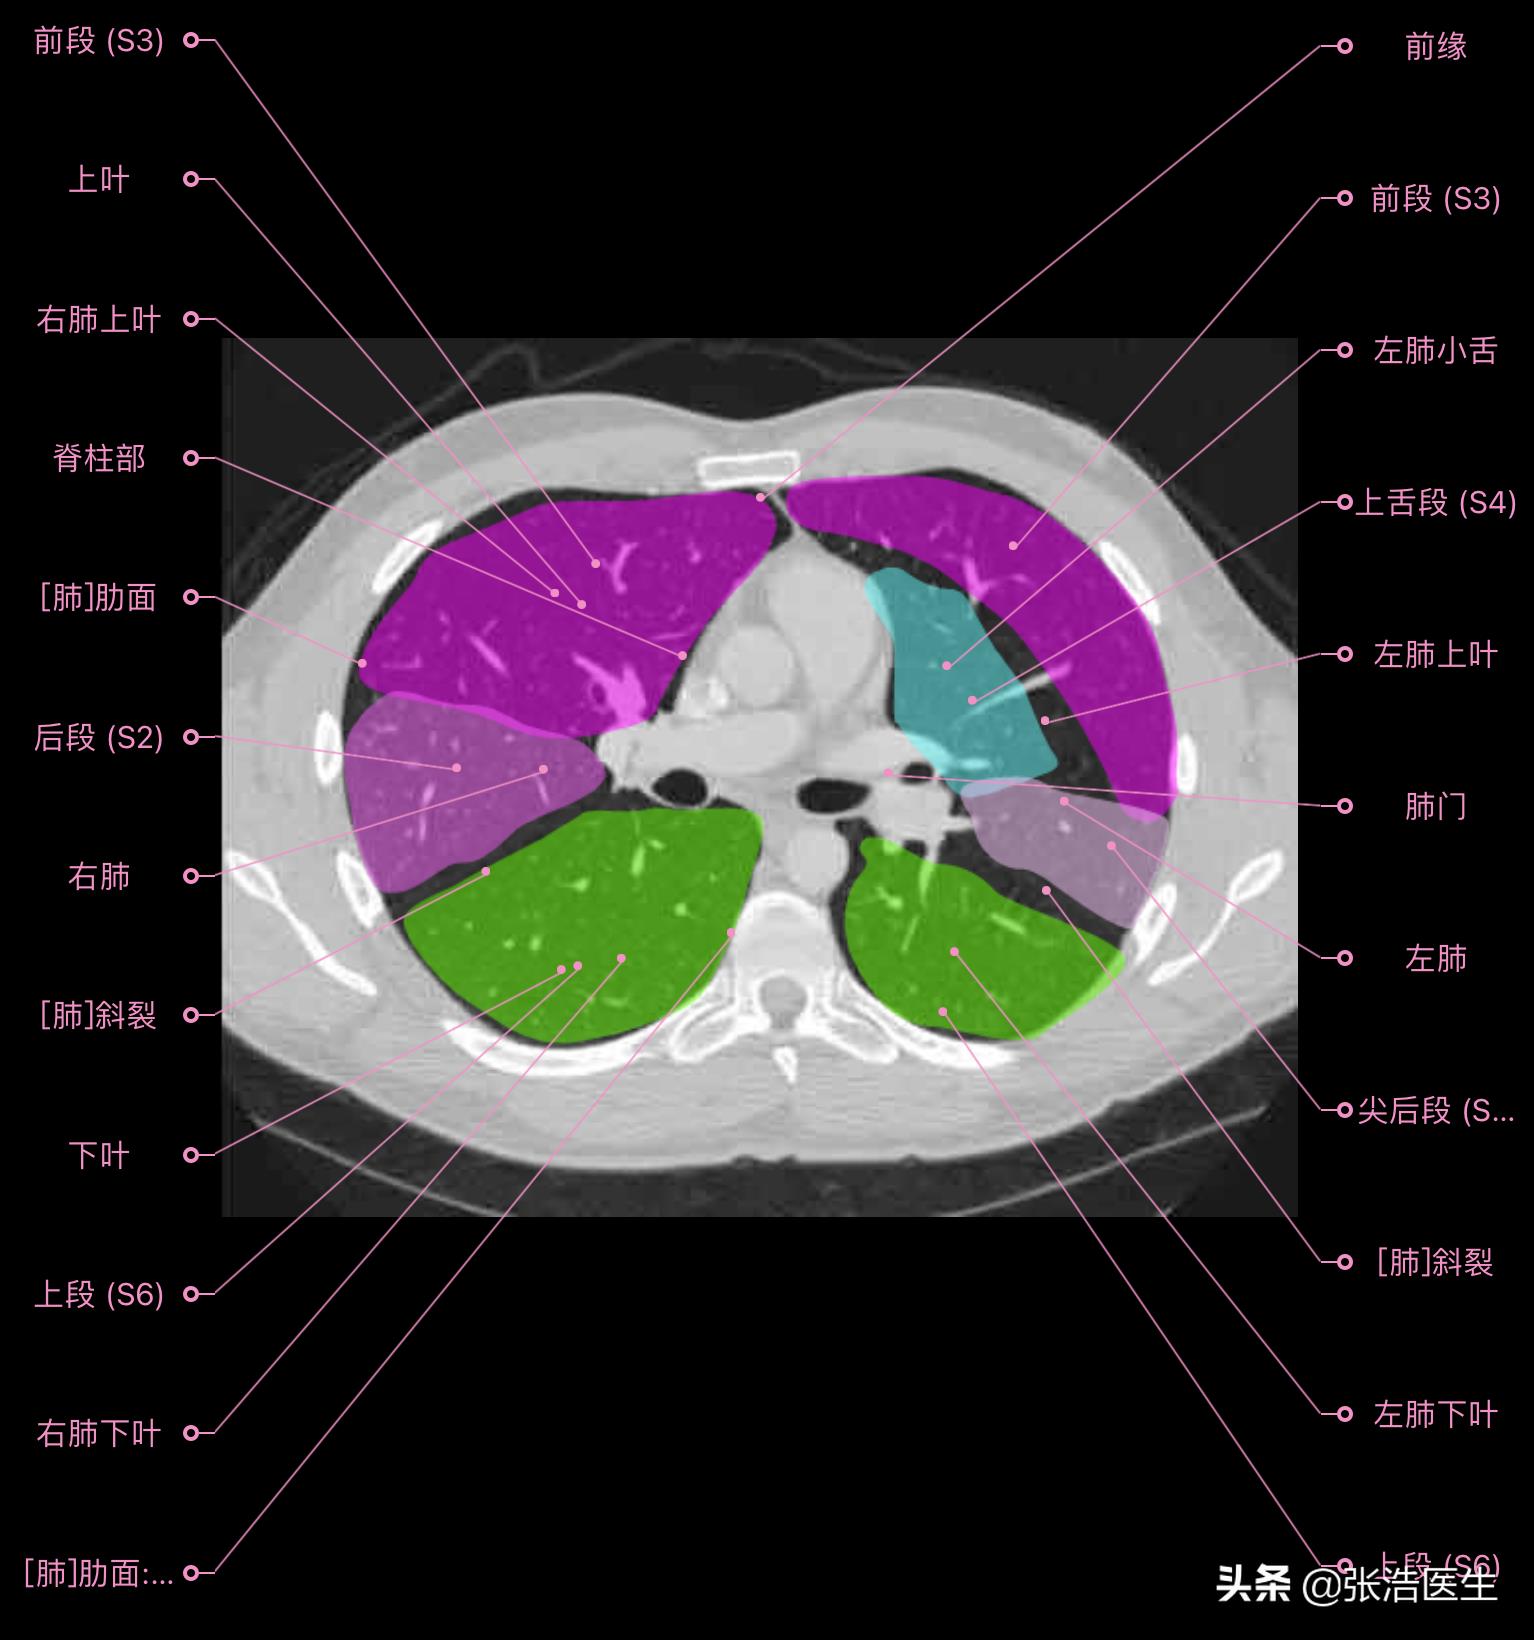

肺部CT横断面高清解剖图谱(图层2)